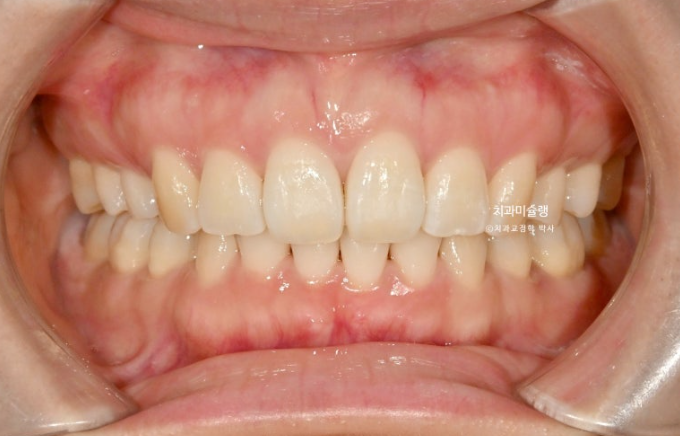

중심선은 정확히 맞아졌습니다.

발치공간도 거의 없어졌습니다.

이제 전후 비교 보겠습니다.

총 치료기간은 3년 2개월, 재제작은 3회 했습니다.

어금니 교합은 뜨는 곳 없이 좋습니다.